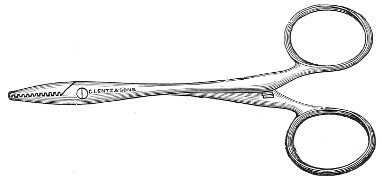

Fig. 24.—Emmet’s perineal scissors.

Fig. 25.—Curved scissors for denuding.